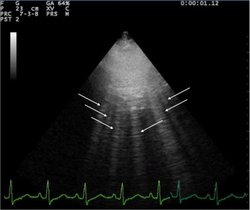

- A lines and B lines

- A lines:

- Appear as horizontal lines

- Indicate dry interlobular septa.

- B lines ("comets"):

- White lines from the pleura to the bottom of the screen

- Highly sensitive for pulmonary edema, but can be present at low wedge pressures